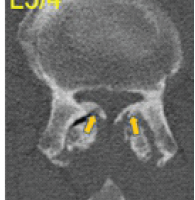

The patient was taken to the operating room for wound exploration under general anesthesia. Intraoperatively, the rod was found traversing the subcutaneous plane, superficial to the flexor digitorum superficialis, flexor carpi radialis, and palmaris longus, and above the dorsal interossei muscles. None of the neurovascular structures or tendons were injured (Fig. 3). The rod was carefully removed under direct vision. The wound was extensively irrigated with normal saline, betadine, and hydrogen peroxide. Hemostasis was achieved, and skin closure was done with Ethilon 3–0 sutures over a glove drain.

Figure 3: Intraoperative findings and assessment. Showing (a) intact flexor tendon function and (b) preserved neurovascular integrity post-rod removal.